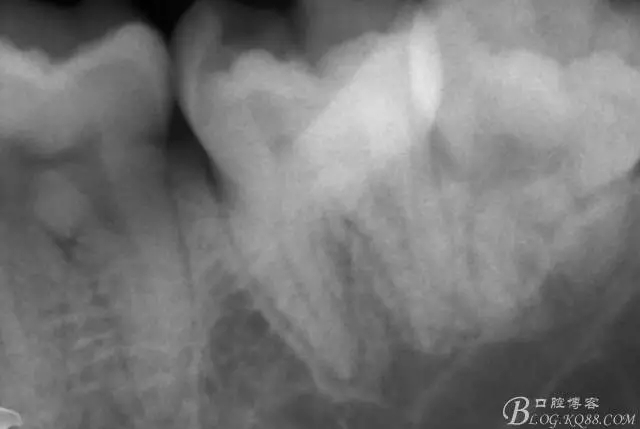

第二次復(fù)診,37叩(+-)。去除暫封物,沖洗,8號(hào)~12號(hào)挫疏通根管,15號(hào)挫用VDW電測(cè)確定根管工作長(zhǎng)度,M : 18mm D :18mm,對(duì)應(yīng)洞緣為標(biāo)記點(diǎn)。其中近中根管感覺是頰舌兩根管,但進(jìn)針感覺又是一根管,運(yùn)用Crown Down Technique預(yù)備法,M3挫登士柏機(jī)動(dòng)配合EDTA,1%次氯酸鈉,生理鹽水交替沖洗。紙尖干燥,封氫氧化鈣。

一周后復(fù)診,37叩(—)。去除暫封物,沖洗,試主尖拍片。

X線示牙膠尖到達(dá)工作長(zhǎng)度,故行AH-PLUSH糊劑配合卡瓦熱牙膠機(jī)運(yùn)用連續(xù)波充法根充,暫封拍根尖片。